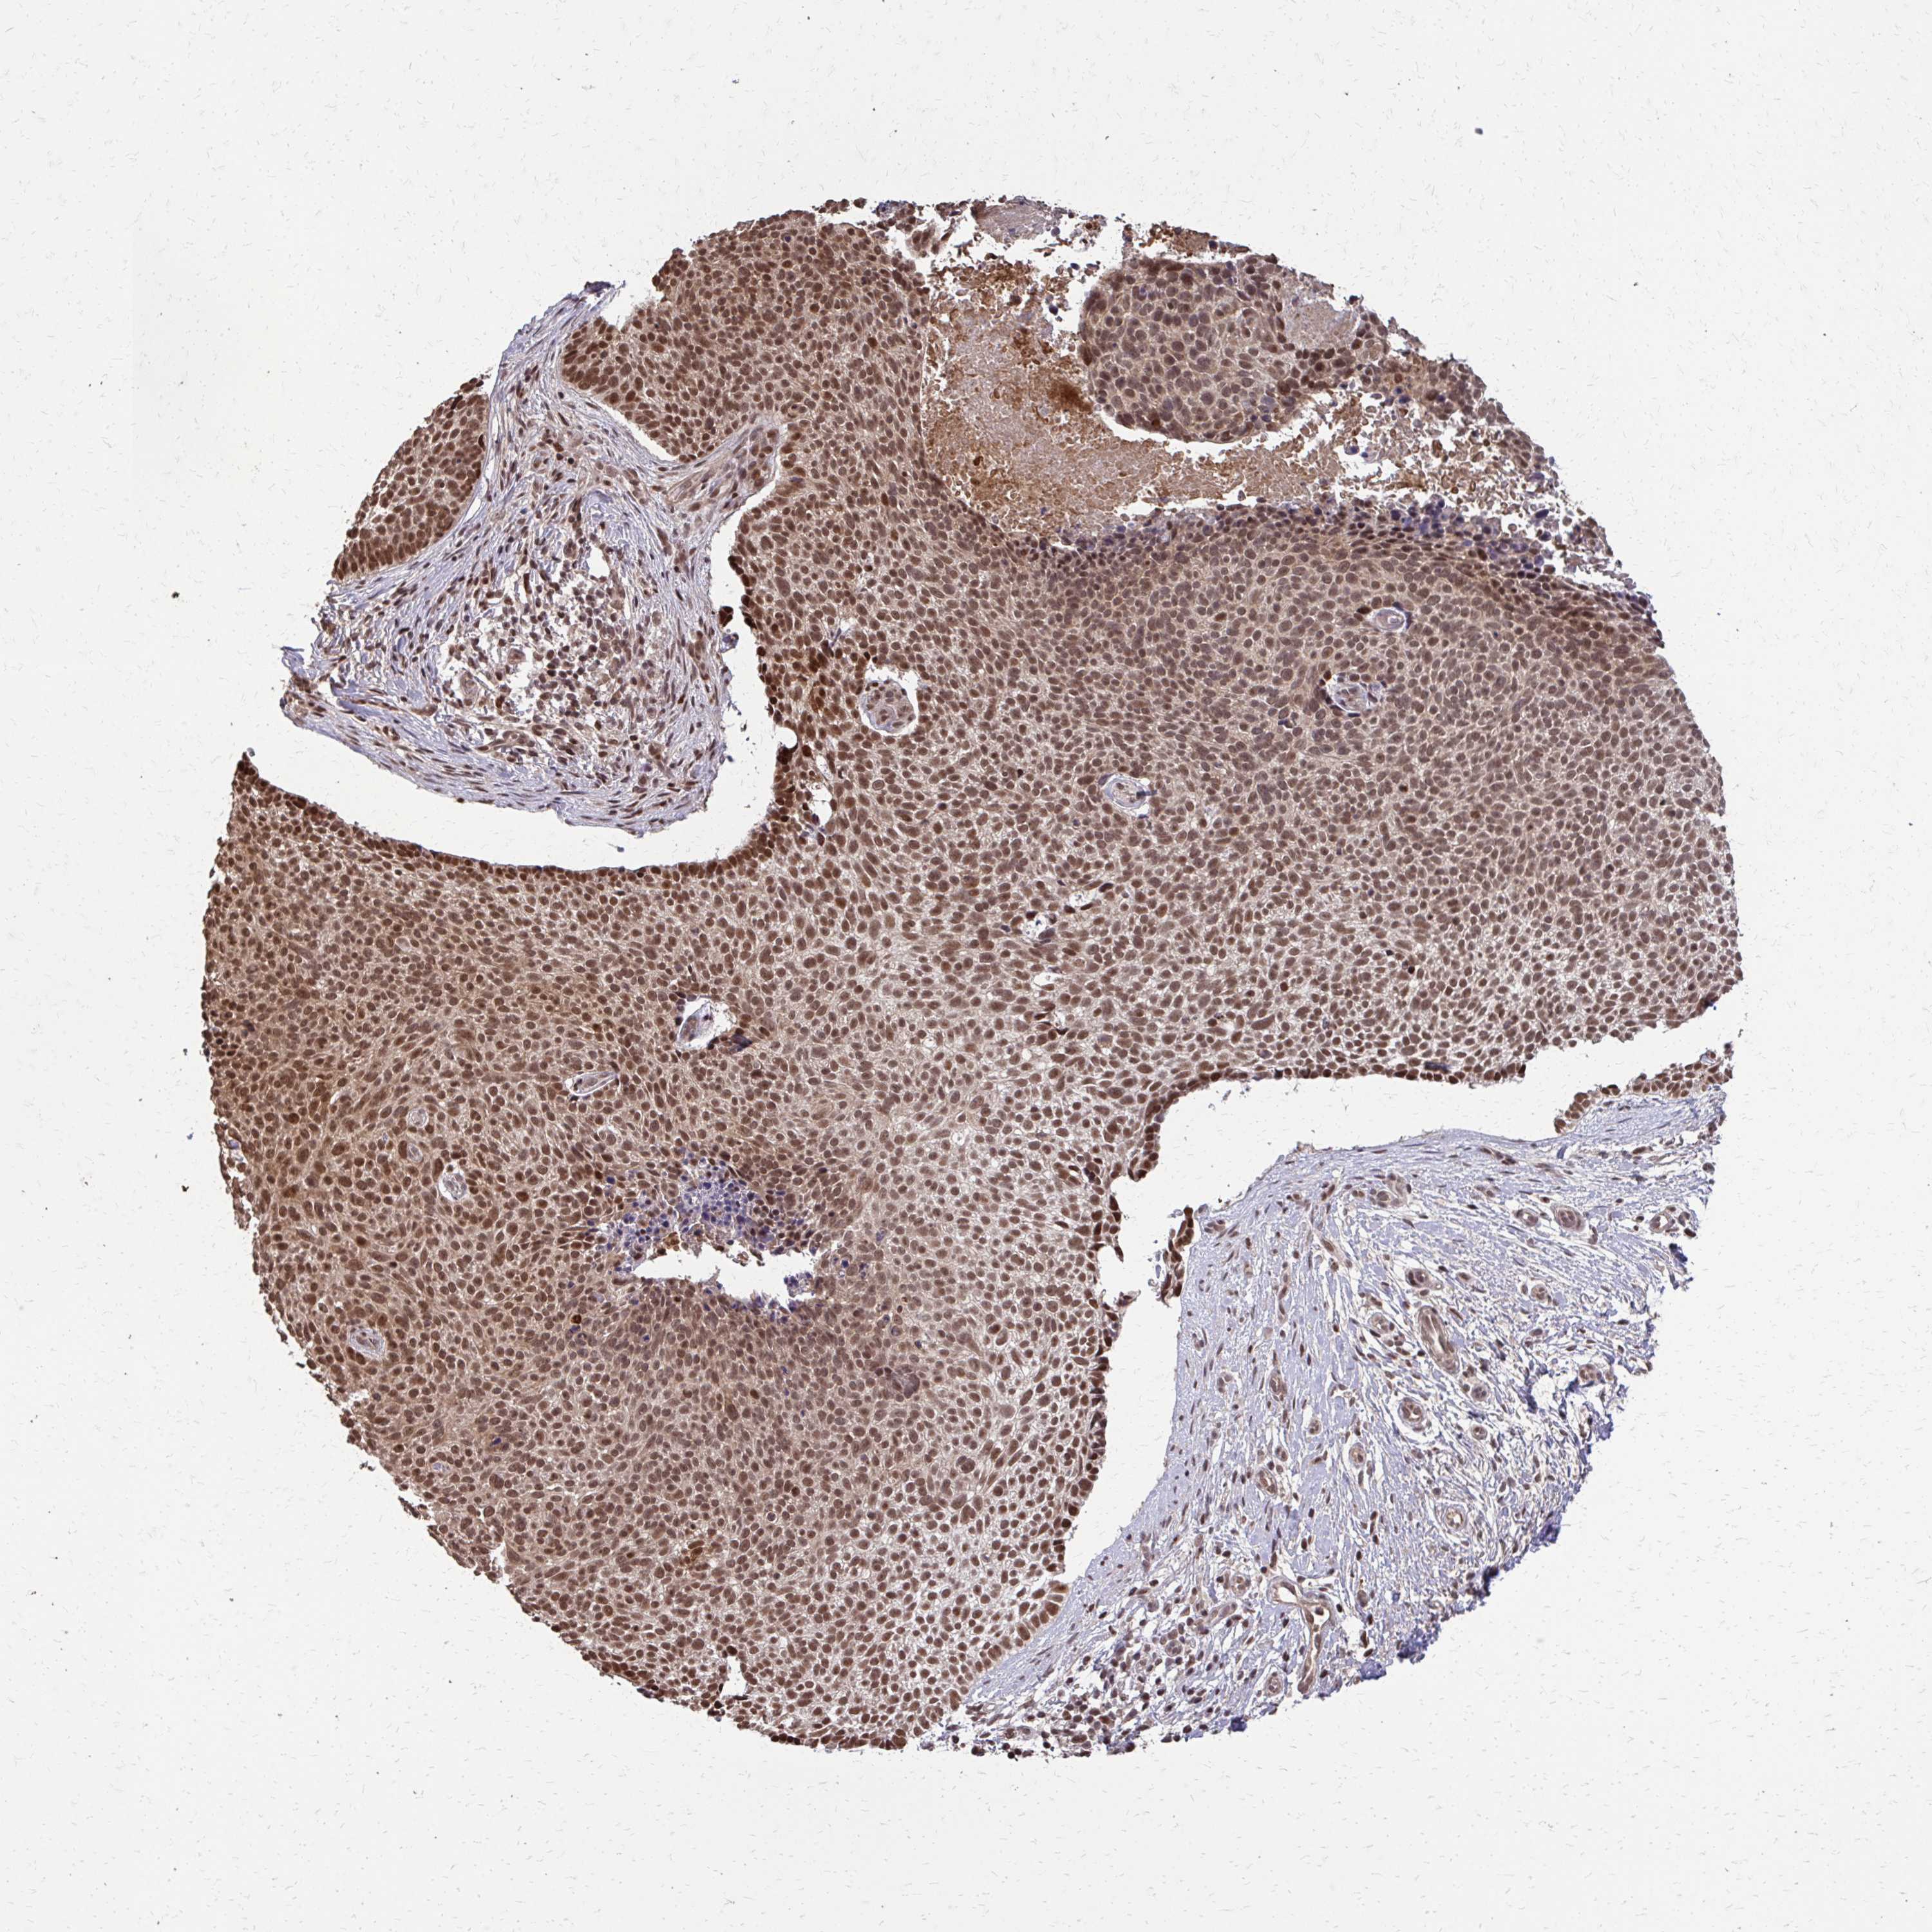

SKIN CANCER - Protein expressioni

A mouse-over function shows sample information and annotation data. Click on an image to view it in a full screen mode. Samples can be filtered based on level of antibody staining by selecting one or several of the following categories: high, medium, low and not detected. The assay and annotation is described here.

Antibody staining in the annotated cell types in the current human tissue is reported as not detected, low, medium, or high, based on conventional immunohistochemistry profiling in selected tissues. This score is based on the combination of the staining intensity and fraction of stained cells.

Each image is clickable and will lead to virtual microscopy that enables deeper exploration of all samples and also displays staining intensity scores, fraction scores and subcellular localization as well as patient and tissue information for each sample.

Antibody HPA055741

Staining

High

Intensity

Strong

Quantity

>75%

Location

Nuclear

Basal cell carcinoma